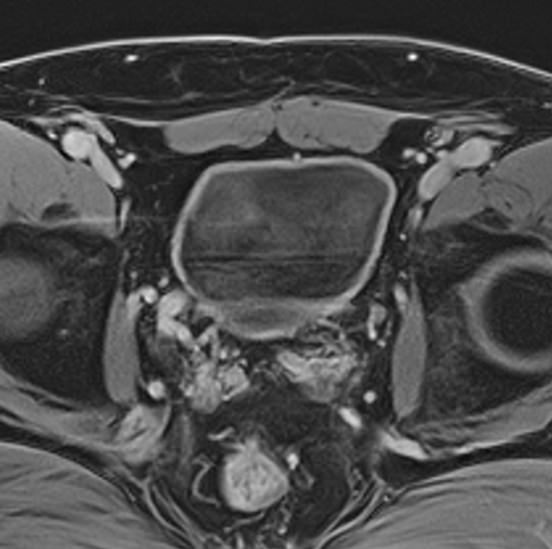

МРТ мочевого пузыря позволяет найти причины возникновения вышеперечисленных симптомов, выявить патологические изменения в мочевом пузыре, окружающих органах и тканях, поставить точный и достоверный диагноз. Процедура безболезненна и при отсутствии противопоказаний безопасна. Метод МРТ не предусматривает использование вредного рентгеновского излучения, поэтому может проводиться неоднократно в течение короткого периода времени, что, например, бывает важно для оценки эффективности лечения.

Но несмотря на высокую диагностическую ценность магнитно-резонансной томографии, в некоторых случаях для улучшения визуализации патологических очагов дополнительно применяется контрастное усиление. В частности, при подозрении на опухолевые образования мочевого пузыря (как первичные, так и метастатического происхождения) требуется внутривенное введение контраста.

Проведение МРТ с контрастированием, в первую очередь, применяется в онкодиагностике. Метод позволяет детально визуализировать опухоль, ее локализацию, размеры, степень прорастания в окружающие ткани, оценить стадию развития. Кроме того, МРТ незаменима в сложных диагностических случаях, при получении неоднозначных противоречивых данных предыдущих обследований.